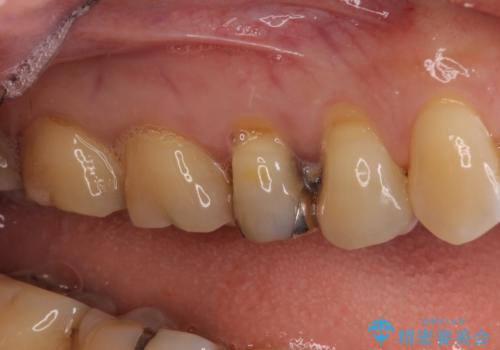

今回はまず欠けた場所を修復して見た目を回復させたのち、ラミネートべニアの仮歯をつくり、しばらく使用して考えて頂きました。メリットやデメリットを説明した結果、外れにくいセラミッククラウンをご選択頂きました。

咬み合わせや元のご自身の歯の色に特徴があったため、セラミッククラウンを修正したり、隣の歯を金属を外して白いつめものに変えたりして経過観察を長めに行いました。

右上の歯に関しても、大きな虫歯があったため、前歯の経過観察の間に治療を行いました。